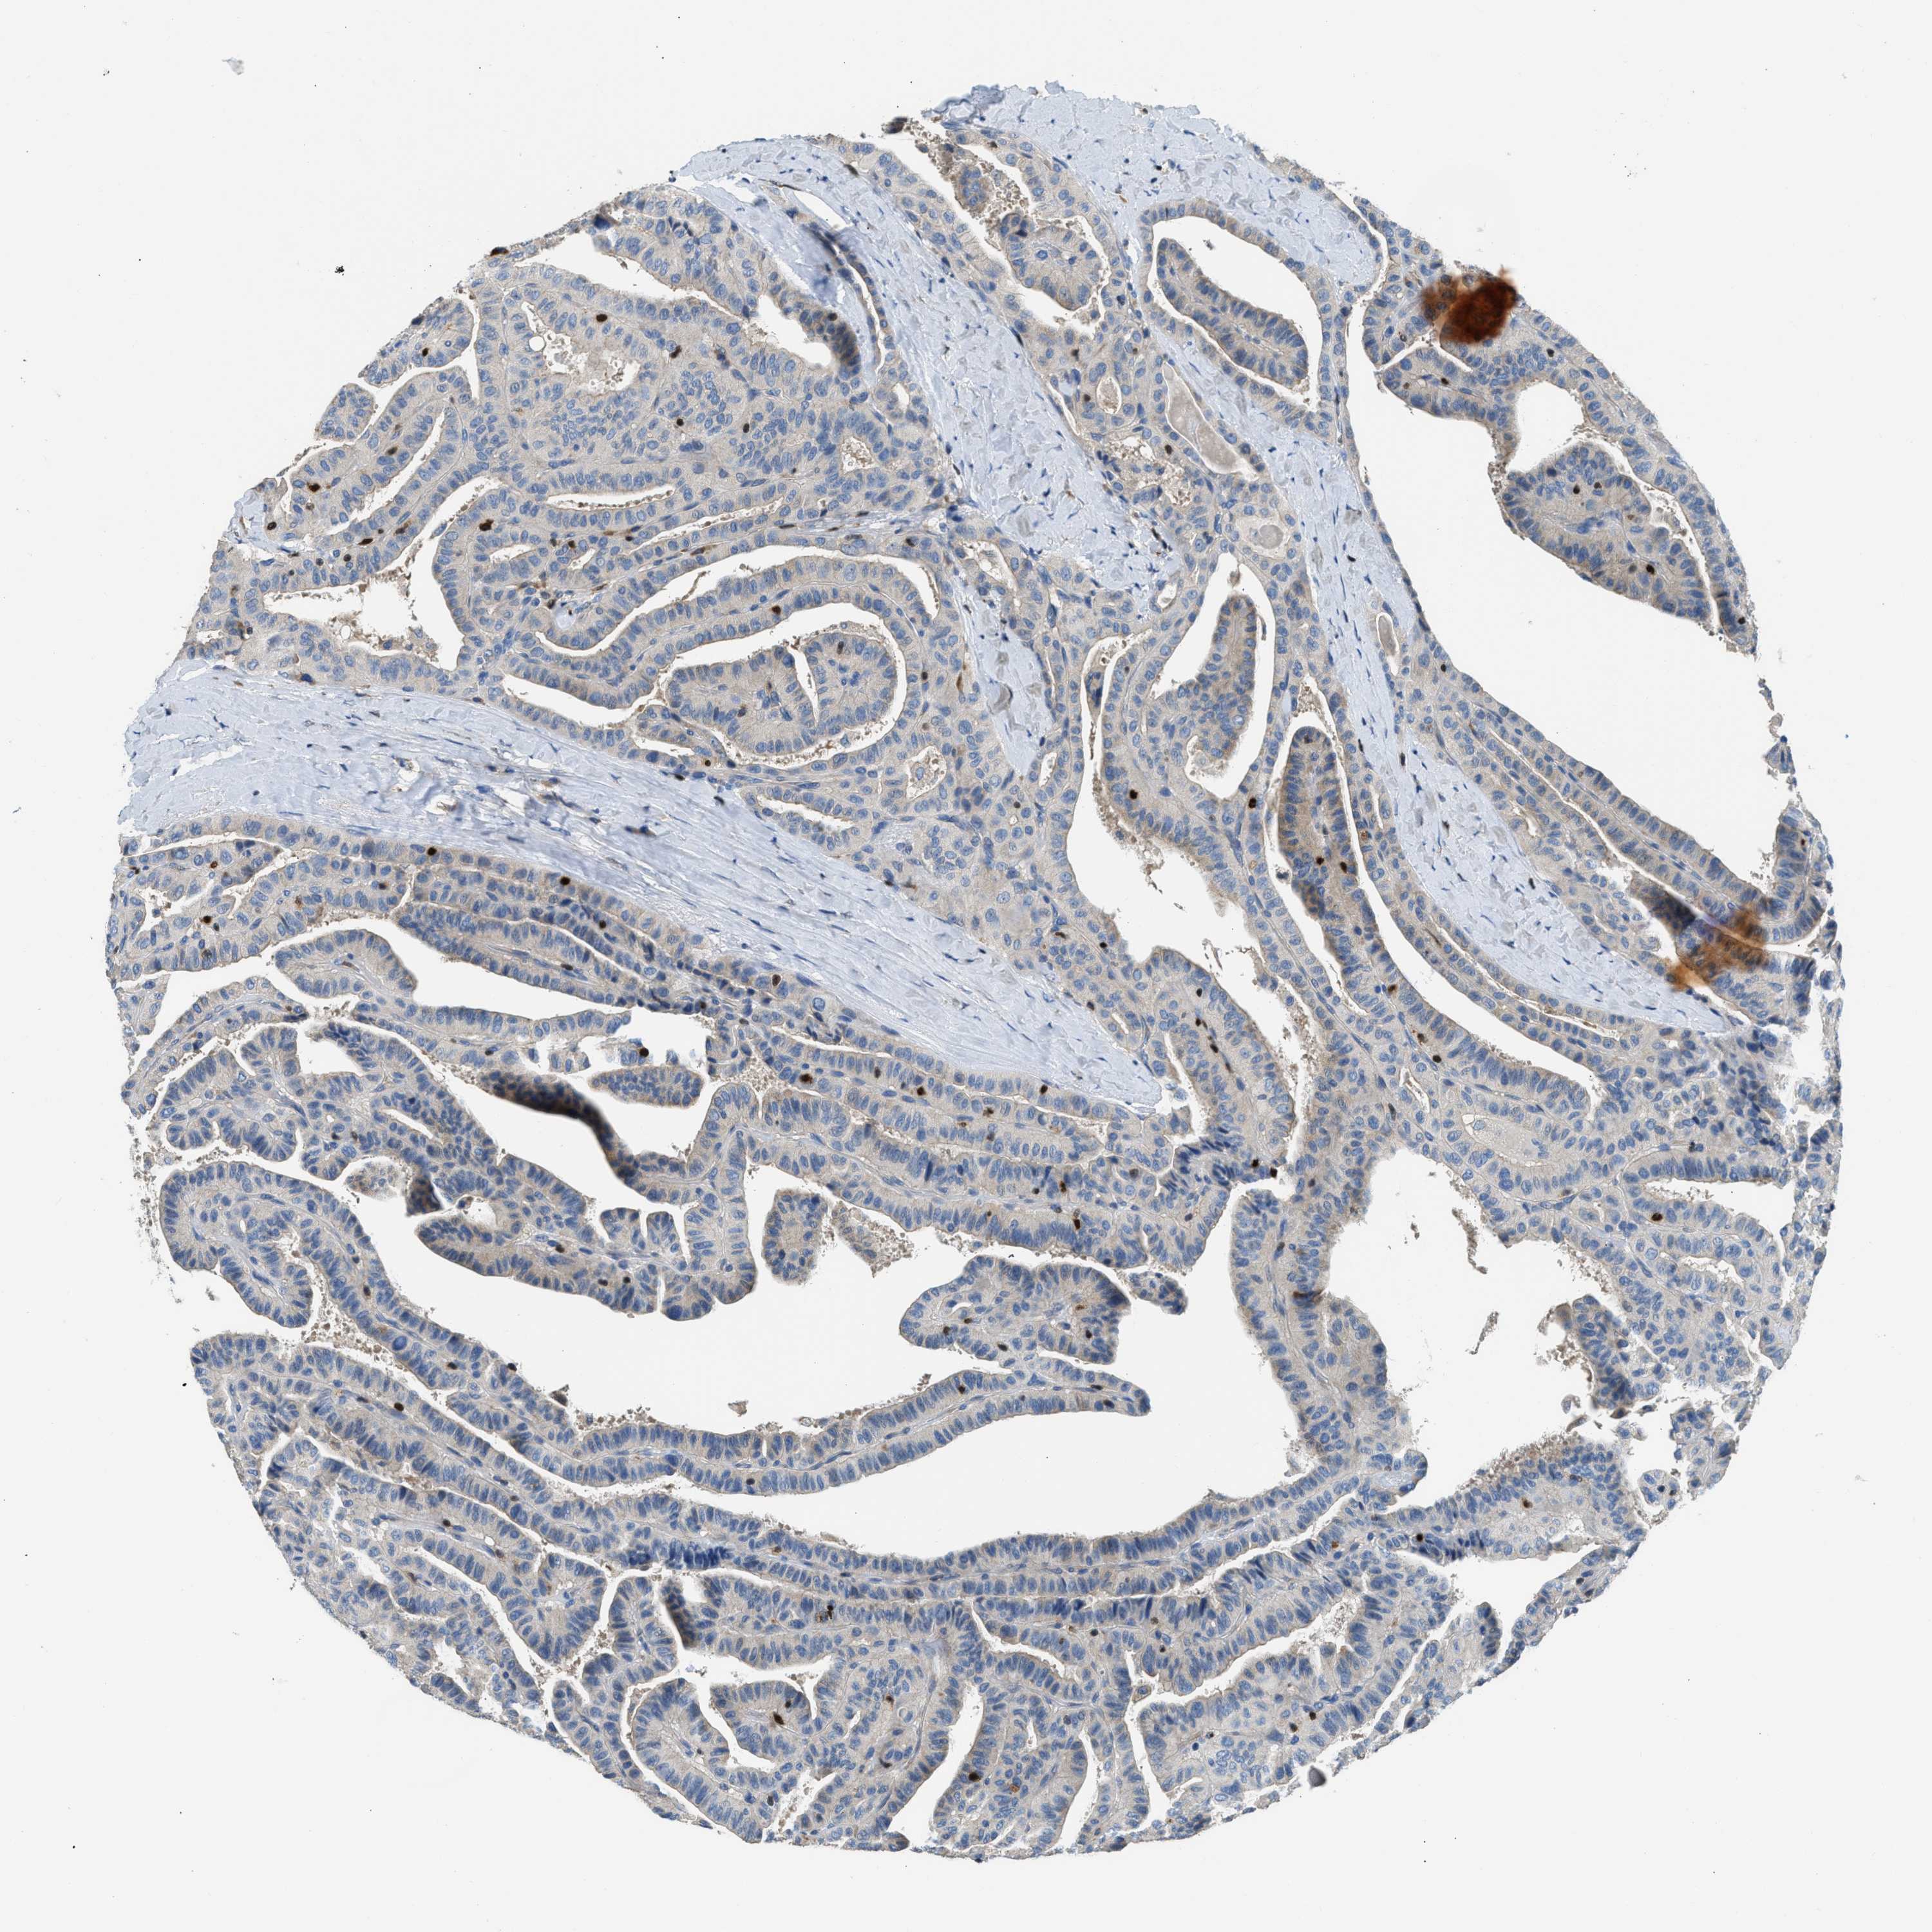

THYROID CANCER - Protein expressioni

A mouse-over function shows sample information and annotation data. Click on an image to view it in a full screen mode. Samples can be filtered based on level of antibody staining by selecting one or several of the following categories: high, medium, low and not detected. The assay and annotation is described here.

Note that samples used for immunohistochemistry by the Human Protein Atlas do not correspond to samples in the TCGA dataset.

Antibody stainingi

Antibody staining in the annotated cell types in the current human tissue is reported as not detected, low, medium, or high, based on conventional immunohistochemistry profiling in selected tissues. This score is based on the combination of the staining intensity and fraction of stained cells.

Each image is clickable and will lead to virtual microscopy that enables deeper exploration of all samples and also displays staining intensity scores, fraction scores and subcellular localization as well as patient and tissue information for each sample.

Antibody HPA018322

Staining

High

Medium

Low

Not detected

Intensity

Strong

Moderate

Weak

Negative

Quantity

>75%

75%-25%

<25%

None

Location

Nuclear

Cytoplasmic/membranous

Cytoplasmic/membranous,nuclear

Papillary adenocarcinoma, NOS

Follicular adenoma carcinoma, NOS